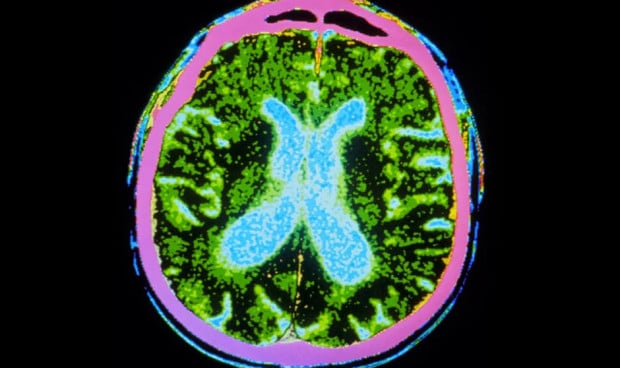

Tras ello, en el momento previo a la cirugía, los investigadores descongelaron esas células y las implantaron en el putamen, "una estructura cerebral profunda con forma de nuez", como se define en la publicación. Todo ello teniendo en cuenta que las neuronas que mueren en la enfermedad de Párkinson "extienden sus tentáculos hasta el putamen".

Así, 'Nature' recoge las declaraciones de Viviane Tabar, neurocirujana del Memorial Sloan Kettering Cancer Center en la ciudad de Nueva York, que fue quien llevó a cabo las cirugías en Estados Unidos. La experta explicó que las células madre fueron inyectadas en 18 sitios a lo largo del putamen en ambos hemisferios con el objetivo de "llenar aproximadamente esa región del cerebro".

En cuanto a los resultados, la revista subraya: "Los escáneres cerebrales mostraron un aumento general en la producción de dopamina, lo que sugiere que algunas neuronas sobrevivieron todo el período de observación de 18 meses, incluso después de que los participantes dejaron de recibir medicamentos inmunosupresores".